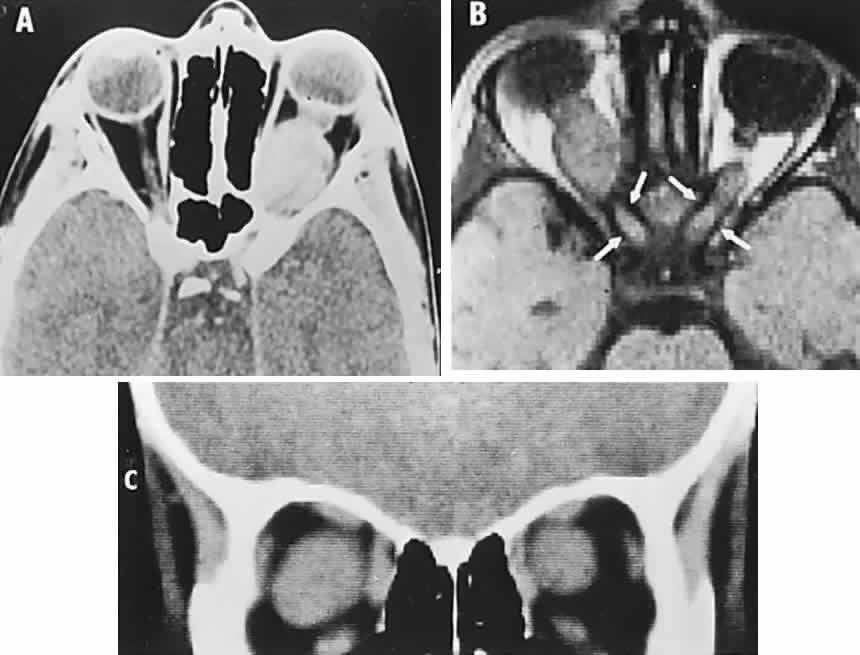

In contrast to transient symptoms and signs of retinal microembolic episodes, a condition of chronic ocular hypoxia (ocular ischemic syndrome) occurs less frequently, resulting from diffuse vascular occlusive disease of the aortic arch or common carotid artery. Acute or chronic occlusion with insufficient collateralization produces an ischemic pseudo-inflammatory uveitis, which variably includes an injected painful globe, corneal edema, aqueous flare and cells, a mid-dilated fixed pupil, rubeosis and iris atrophy, rapidly advancing cataract, either hypotony or elevated intraocular pressure (“neovascular glaucoma”), retinal microaneurysms and new vessel formation, posterior pole and mid-peripheral blot hemorrhages, macular edema, venous dilation and “sausaging,” cytoid infarcts (cotton-wool spots) of the nerve fiber layer, and arterial occlusions (Fig. 7; see Table 4). The hypoxemic fundus changes constitute a picture of venous stasis (low-pressure) retinopathy, perhaps the commonest ocular sign of chronic carotid obstruction.

Fig. 7. Ocular hypoxia with subacute carotid occlusion. The patient complained of a painful red eye. A. Anterior segment shows an irregular, fixed pupil and iris rubeosis (arrows). B. Fundus demonstrates combined retinochoroidal infarction with acute excavation of the optic disc. Arteriography revealed right internal carotid occlusion.